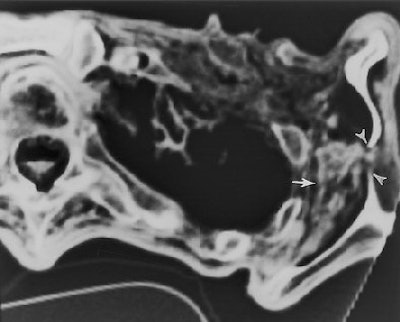

![]() |

| Transverse CT section (obtained on May 3, 1994) through the left shoulder region (caudal to the prehistoric arrowhead) shows an inhomogeneous area of attenuation (dehydrated hematoma, arrow) between the lateral rib cage and the scapula. Note the discontinuity in the ossified body of the scapula and the wispy soft-tissue opacity (hematoma) that extends through the bone defect (arrowheads). Authors speculate that the arrowhead and a portion of the arrow shaft penetrated the scapula in this location and that blood from the deep hematoma followed the arrow track into the subcutaneous tissues. Fig. 23, Murphy WA, zur Nedden D, Gostner P, et al. "The Iceman: Discovery and Imaging," Radiology 2003; 226:614-629. |

"Furthermore, it is speculated that when the arrow was withdrawn, the overlying scapula interfered and caused the arrowhead to separate from the shaft. Thus, the arrowhead remained trapped between the rib cage and the scapula," Murphy and colleagues wrote. "The fact that the arrow entered the iceman from behind suggests that the manner of death was either accidental or homicide."